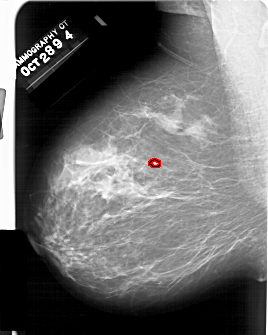

A_1438_1.LEFT_MLO

LEFT_MLO LINES 6361 PIXELS_PER_LINE 5086 BITS_PER_PIXEL 12 RESOLUTION 43.5 OVERLAY

FILE: A_1438_1.LEFT_MLO.OVERLAY

TOTAL_ABNORMALITIES 1

ABNORMALITY 1

LESION_TYPE CALCIFICATION TYPE PLEOMORPHIC DISTRIBUTION CLUSTERED

ASSESSMENT 4

SUBTLETY 2

PATHOLOGY BENIGN

TOTAL_OUTLINES 1

BOUNDARY